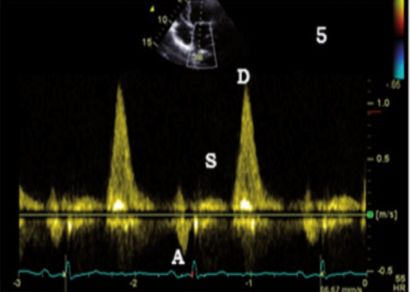

肺静脉血流频谱改变